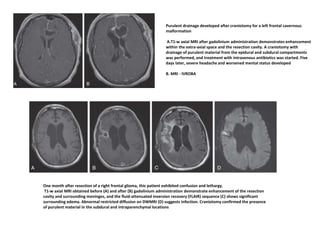

Purulent drainage developed after craniotomy for a left frontal cavernous

malformation

A.T1-w axial MRI after gadolinium administration demonstrates enhancement

within the extra-axial space and the resection cavity. A craniotomy with

drainage of purulent material from the epidural and subdural compartments

was performed, and treatment with intravenous antibiotics was started. Five

days later, severe headache and worsened mental status developed

B. MRI - IVROBA

One month after resection of a right frontal glioma, this patient exhibited confusion and lethargy.

T1-w axial MRI obtained before (A) and after (B) gadolinium administration demonstrate enhancement of the resection

cavity and surrounding meninges, and the fluid-attenuated inversion recovery (FLAIR) sequence (C) shows significant

surrounding edema. Abnormal restricted diffusion on DWMRI (D) suggests infection. Craniotomy confirmed the presence

of purulent material in the subdural and intraparenchymal locations